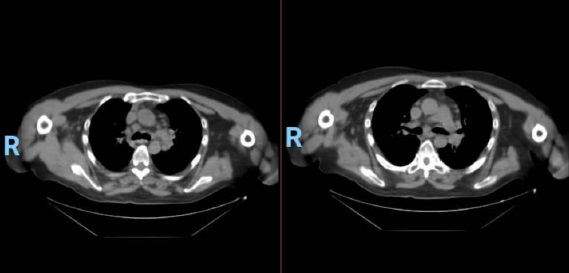

En la tomografía computada de tórax en ventana pulmonar se identifica un patrón micronodular con distribución perilinfática y difusa en ambos hemitórax. Este hallazgo se acompaña de un engrosamiento peribronquial notable, así como de opacidades en vidrio deslustrado, que predominan en las zonas subpleurales y en las regiones posteriores de ambos pulmones.

En la tomografía computada de tórax en ventana mediastínica se observan múltiples adenopatías localizadas en diversas áreas del cuello y mediastino. Estas adenopatías se distribuyen en las cadenas yúgulo-carotídeas, en ambas regiones supraclaviculares y a lo largo del mediastino, abarcando específicamente las siguientes áreas: la región paratraqueal superior derecha, los espacios retrocavo-pretraqueal y prevascular, la zona subcarinal, la ventana aortopulmonar y en la región de la arteria mamaria (AM). La presencia de estas adenopatías sugiere un compromiso linfático difuso en estas zonas.